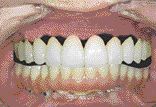

FIGURE 10--Post-treatment smile.

ABSTRACT: Attachment-retained RPD is not an outdated treatment modality. It is even more contemporary in today’s appearance-oriented society than when it was first introduced. There is significant number of patients who could benefit from this treatment option, both short and long term. However, lack of proper education, overwhelming number of attachments available on the market, … Read more